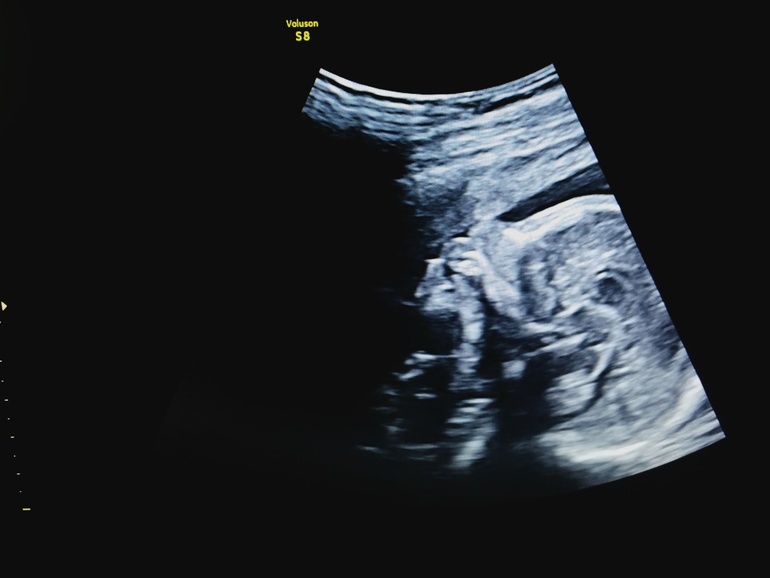

Пол малышаМы сегодня сделали 2 скрининг. Девушка меня долго томила... Минут 20 говорила, что все хорошо. А я чуть с койки не упала, выглядывая половую принадлежность😊🐱 сама долго ждала и не ходила на платное... А смысл, томила себя на медленном огне. И в итоге вскользь "у вас мальчик". Эти эмоции, желание плакать и смеяться, уииии!!!